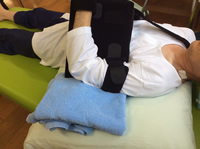

手術後の装具固定

|

腱板修復術後は修復した部分の回復を阻害しないため、一定期間の固定を行います。 腱板修復術を受けられた方は術後3~6週の間、装具を装着して頂きます。 装具の大きさは断裂の程度によって多少異なる場合があります。 図は当院で使用している装具となります。 |